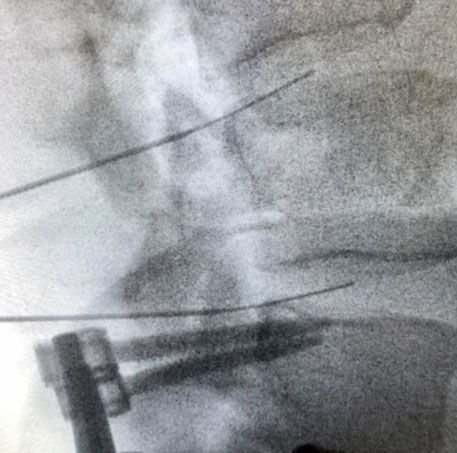

Initial treatment options for management of painful lumbar degenerative disc disease (lumbar discogenic pain) may include lifestyle modifications, medications, physical therapy, chiropractic, and/or a home exercise program. In many cases, these conservative measures will allow for excellent recovery. If a patient is still experiencing significant pain despite the aforementioned treatment options, there are a variety of interventional (procedural) options available. Epidural steroid injections may be considered to decrease the inflammatory component of the pain. Using fluoroscopy (low-dose intermittent x-ray) for procedural target identification and precise needle guidance, needles used to access the epidural space and placed in close proximity to the target disc. Once the needles are properly placed, corticosteroid (“cortisone”) is instilled through the needles to coat the painful disc(s). This helps to decrease inflammation and pain for individuals with lumbar discogenic pain. Alternative interventional options may include pulsed radiofrequency of the sinuvertebral nerves, intradiscal corticosteroid (cortisone) injections, or intradiscal platelet-rich plasma (PRP) injections. With performing pulsed radiofrequency of sinuvertebral nerves, fluoroscopy is once again used for procedural target identification and precise needle guidance. Then, specialized needles are placed in close proximity to the sinuvertebral nerves of the symptomatic disc. After testing is completed, a signal is produced by a generator and transmitted to the tip of the specialized needle to “stun” the nerves that sense and transmit sensory information from the posterior 2/3 of the disc. Finally, with intradiscal corticosteroid or PRP injections, a needle is placed via x-ray (fluoroscopic) guidance in the centre of the symptomatic disc followed by instillation of either corticosteroid or PRP solution. Corticosteroid helps to manage pain by decreasing inflammation; PRP aids in management of pain by decreasing inflammation and improving signaling of cells that contribute to tissue healing. Read on to learn more about provocative lumbar discography as well as intradiscal PRP injections. If all conservative measures have been exhausted, referral to spine surgery for consideration of fusion surgery may then be considered.

Provocative lumbar discography is the gold standard diagnostic test to precisely confirm or exclude the intervertebral disc as a source of chronic low back pain. Using fluoroscopic (x-ray) guidance, needles are placed within two or more discs and pressurized using contrast dye. Based on patient response (i.e. whether the patient’s typical low back pain is reproduced or not) and imaging findings such as fissures (tears) within the disc(s), a diagnosis of painful lumbar degenerative disc disease (lumbar discogenic pain) can be confirmed or ruled out as a source of chronic low back pain.